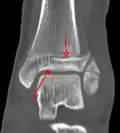

Une fracture triplane de la cheville vue par TDM

Les tomodensitogrammes peuvent être indiqués en cas de risque de fracture fragmentée ou de fracture impliquant la surface articulaire[9]. Cette imagerie peut être utilisée pour la planification chirurgicale.